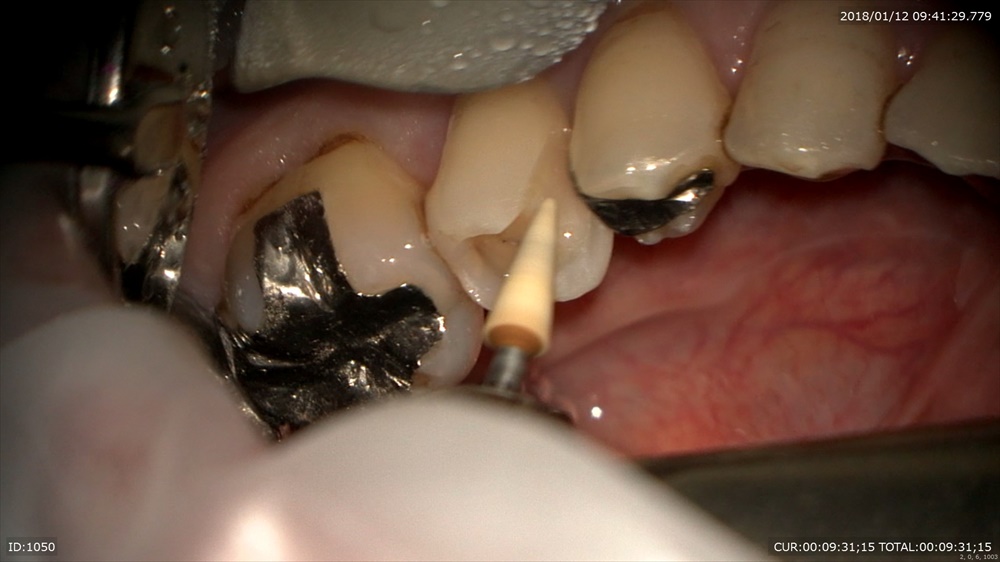

次は精密根管治療

2本同時に治療中

右が術前左が術後綺麗になってきました。

根管の先まで見えます。マイクロスコープでしか確認ができません。痛みがとれない。ばれが引かないなど必ず原因があるはずです。

次回最終的なお薬ですね。4回で終了。ちょっと回数かかりすぎです。反省。